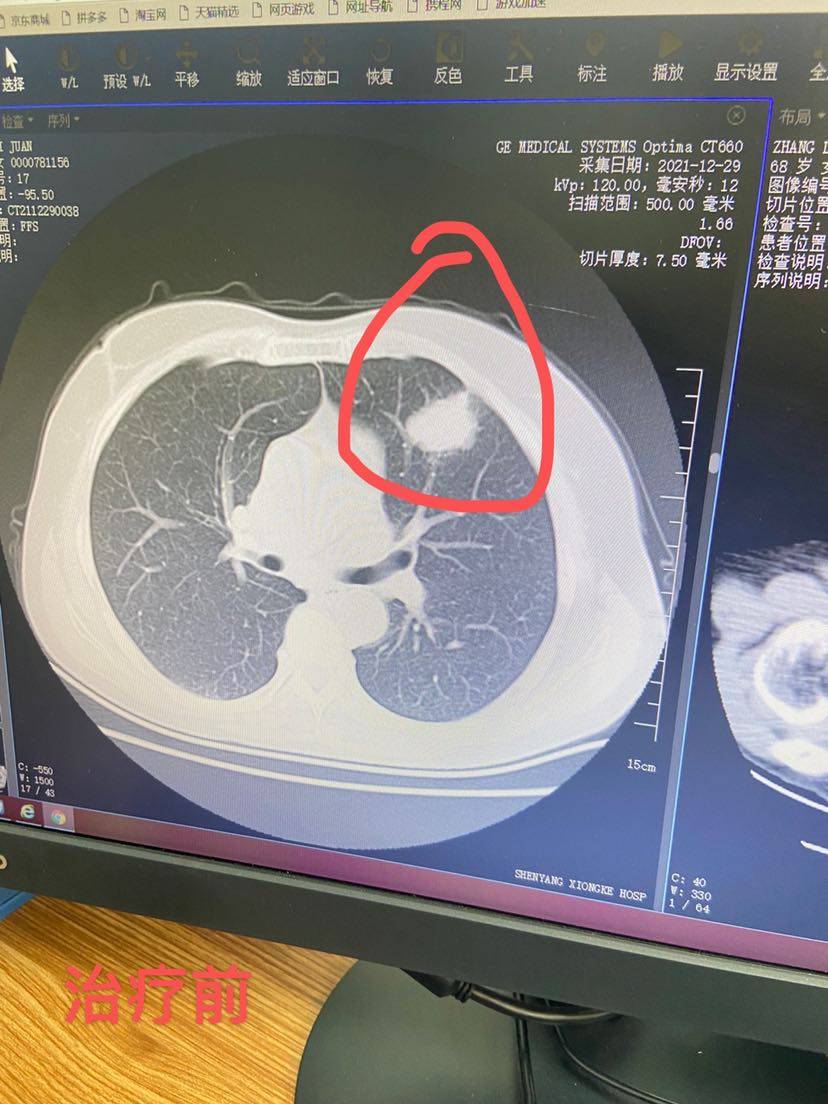

看样子得缩小50%